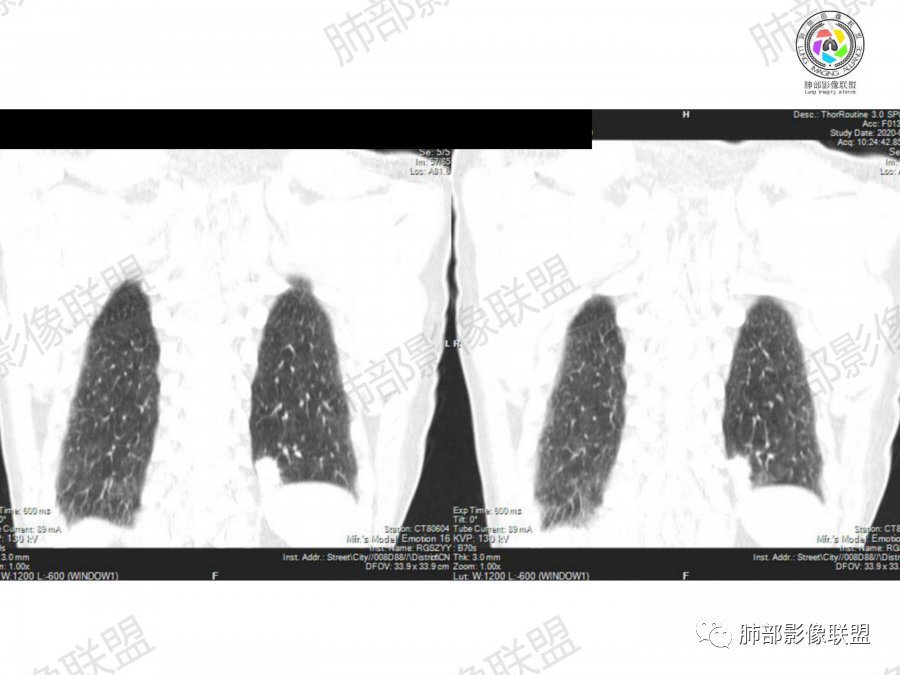

1、老年男性,大量吸烟史,无症状,体检左下肺孤立结节。

2、影像表现:无肺气肿背景、定位左肺下叶后基底段,不规则结节、与支气管关系不明确,部分边缘平直、部分膨隆,病变与胸膜宽基底相连,病变与胸膜糊墙征,病变周围见细、长、软毛刺,病变密度比较均匀。影像总体倾向炎症、符合肺组织慢性炎症伴机化。

综合分析:

该例病变虽然为老年男性,无肺气肿背景,无临床症状、长软毛刺、刀切边缘、糊墙,病灶密度均匀,周围支气管无截断,病灶密度均匀,基本为良性炎性病变特征,但并不是绝对,工作中应该建议治疗后随访排外其它。